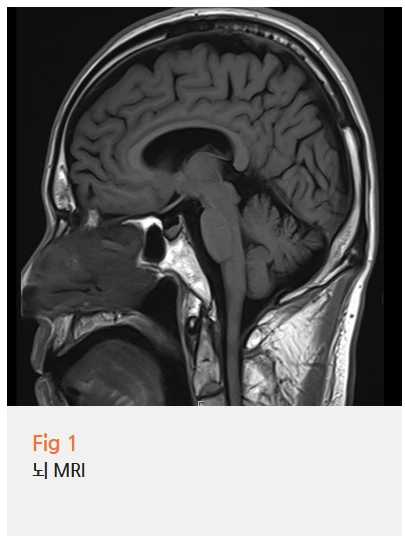

뇌 쪽 이상을 걱정하고 오신 분들은 뇌 MRI를 먼저 확인하는 게 맞아요.

대학병원에서도 이미 검사를 받으셨지만, 저희에서도 다시 한번 면밀히 살펴봤어요.

결과는 동일했습니다. 두통을 유발할 만한 뇌혈관 이상이나 구조적 문제는 없었어요.

그런데 저는 여기서 멈추지 않았어요.

뇌에 이상이 없다는 게 두통의 원인이 없다는 뜻은 아니거든요.